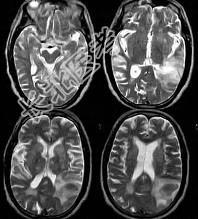

- 单项选择题男,76岁, 突发神志不清,伴呕吐6小时, MRI检查如图所示,最可能的诊断为 ( )

A、出血性脑梗死

B、肿瘤出血

C、原发脑出血

D、脑结核

E、脑脓肿